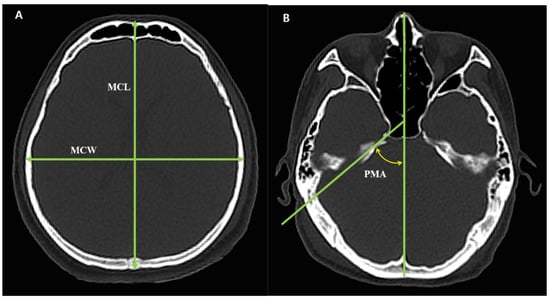

Using the DICOM viewer, the MCL was measured at the longest point of the anterior–posterior length of the skull, and the MCW was measured at the longest point of the left-right width of the skull. The CI was calculated by dividing the MCW by the MCL and multiplying by 100. The PMA was measured as the angle between the petrous ridge and the midline [] (Figure 2). Cranial morphology was classified into three types according to two classification methods, respectively. In the CI method, brachycranic was defined as CI ≥ 80%, mesocranic as 75.0% < CI < 80%, and dolichocranic as CI ≤ 75%. In the PMA method, brachycranic was defined as PMA ≥ 54°, mesocranic as 46° < PMA < 54°, and dolichocranic as PMA ≤ 46° [,]. All measurements were conducted independently by two researchers, who identified the locations, lengths and angles. The measurements from each researcher were averaged.

Figure 2. Two methods for cranial morphology measurement. (A) CI measurement method and section level; (B) PMA measurement method and section level. MCL, Maximum cranial length; MCW, maximum cranial width; PMA, Petrous ridge–midline angle; Cranial index (CI) = (MCW/MCL) × 100.